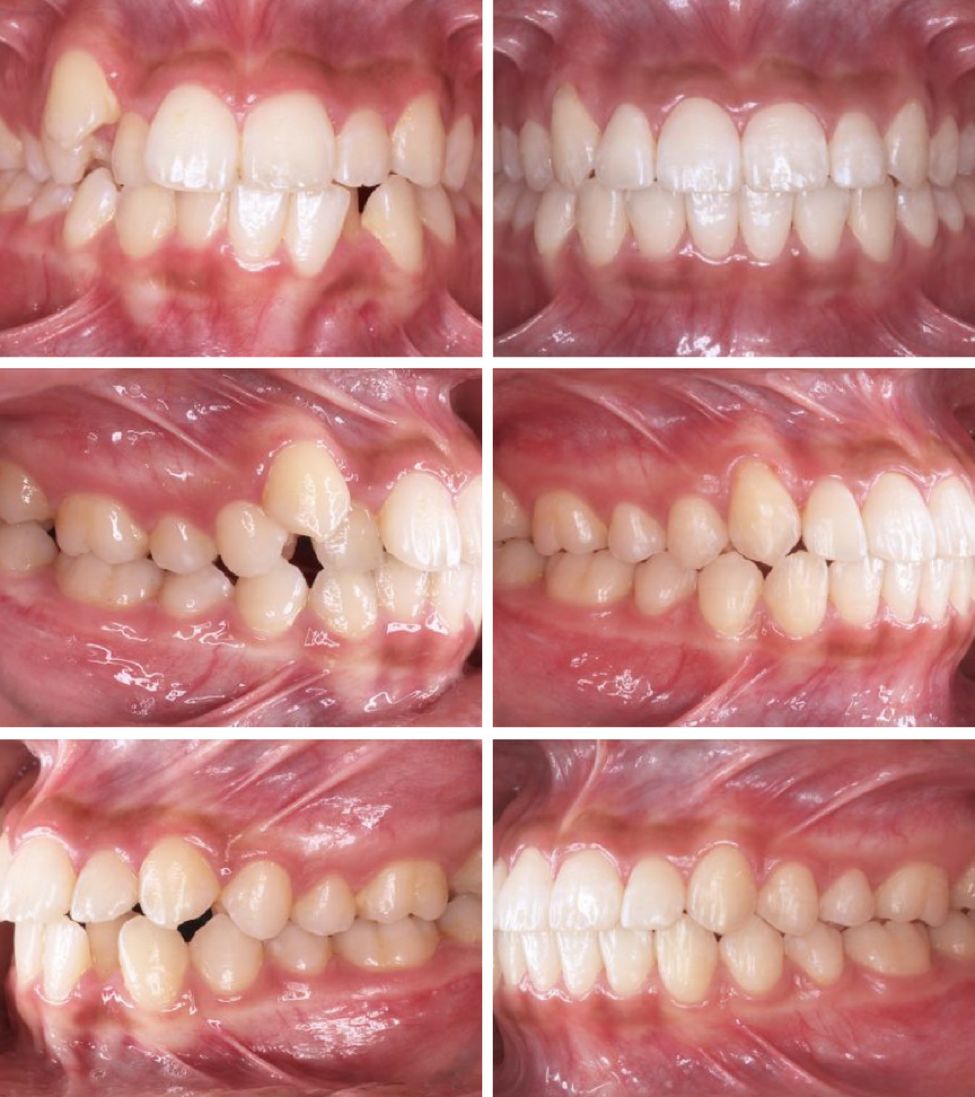

CASE 4

关键词

地包天、牙齿拥挤、拔牙

其实我们做过很多地包天的案例都没有拔牙的~

也有少数cases是比较严重的地包天,需要拔掉下排两颗牙齿把下排推进去很多。比如上面这个姑娘。

这个变化是相当大了!时间也比较久,65幅牙套,21个月

65

21

CASE 5

过咬合、凸嘴

这个弟弟虎牙非常的调皮,下牙也歪。这个case没有拔牙,因为上下差不大,总共是59个牙套,时长18个月,虎牙严重的移位,要让这颗牙回来时间就比较长,如果只是简单排列不齐,那一般一年之内可以搞定。

59

18